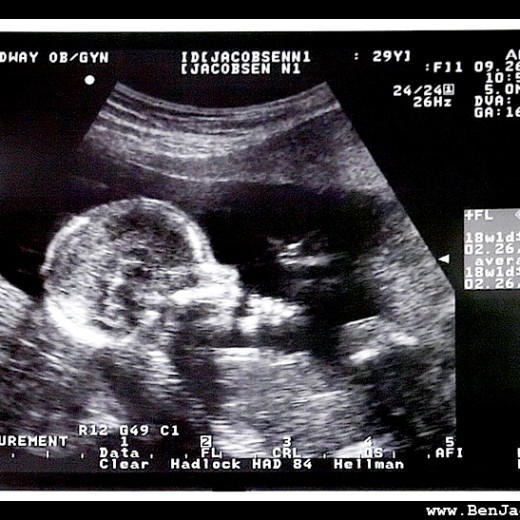

16 week baby update!

We had our 16 week checkup today… Awesome visit as we spent nearly 15 minutes checking out the baby on the ultrasound. 10 fingers, 10 toes, 2 kidneys, 2 lungs 4 heart chambers, the head of an 18 week old (just like Dad?!) bones, everything but the sex… Even if we’d wanted to know the…